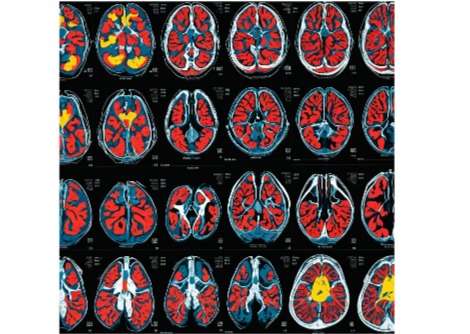

كما درس الفريق كيفية تأثير لاك-في على خلايا AgRP، فوجدوا أنه يعمل على بروتين يسمى قناة KATP الموجودة في هذه الخلايا، وهو بروتين يساعد في تنظيم نشاطها.

يقول الدكتور هي:

"عندما يُنشّط لاك-في هذه القنوات في خلايا AgRP، يقل نشاطها. وعندما قمنا بحجب هذه القنوات بالأدوية أو بالتقنيات الجينية، لم يعد لاك-في قادرًا على كبح الشهية، مما يؤكد أن قناة KATP ضرورية لتأثيره."